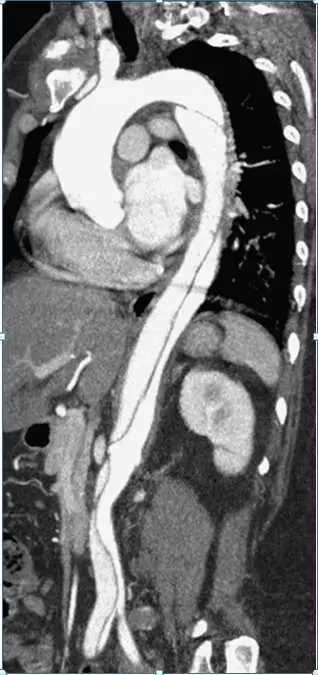

圖片為對比增強電腦斷層(contrast-enhanced CT)矢狀面重建影像,清楚顯示:

- 主動脈內膜瓣(intimal flap):可見一條縱向線性低密度結構將主動脈管腔一分為二,形成真腔(true lumen)與假腔(false lumen)

- 剝離範圍:起自降主動脈近端(左鎖骨下動脈以遠),向下延伸至腹主動脈,符合 Stanford B 型(升主動脈未受累)

- 升主動脈:外觀正常,無內膜瓣,排除 Stanford A 型

- 假腔:較真腔寬大,對比劑充填較慢,此為慢性 / 亞急性剝離的典型表現

- 腎臟及腸系膜血管灌流尚存,未見明顯器官缺血跡象

此影像與臨床情境(高血壓病史、3 週前突發撕裂性背痛)完全吻合 Stanford type B 主動脈剝離。